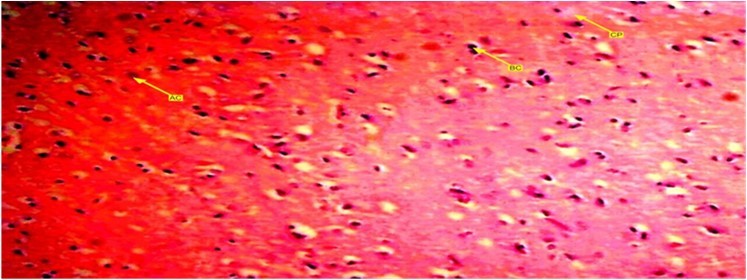

A buffered formalin bottled containing 10% solution was used and preserved the brain tissues of experimental wistar rats. Each bottle was labeled up and allowed to stand for 72 hours in order to ensure maximum penetration. After that, they were placed in ascending dehydration with ethanol solution. First 70% of ethanol solution was used for an hour then subsequent 95% solution and lastly alcohol solution for absolute dehydration. Tissue clearance took place in three (3) subsequent changes of xylene each lasting for 15 minutes. Tissue embedding with paraffin wax was carried out overnight to form blocks which were trimmed and sectioned at 5micro thickness using rotary microtome. Warm water at 28 degree Celsius bathed the tissue samples and dried up on an aluminum glass slides with heamotoxylin and eosin staining method which cleared up 95% of the xylene in alcohol and washed up in running tap water for 15 minutes. The differentiated section o turned blue after addition of 1% alcohol and eosin for 1 minute. The stained sections were viewed under a light microscope and photomicrographs of the stained tissues were taken. Figure 1, Figure 2, Figure 3

Figure 2.Showed a photomicrograph of anterior pituitary gland of female wister rat treated with combined pills for 72 days. It causes decrease in acidophilic and basophilic cells compared with control group. Chomophobes are also in less proportion compared with control group. Those in this group tend to have more decreased cells.